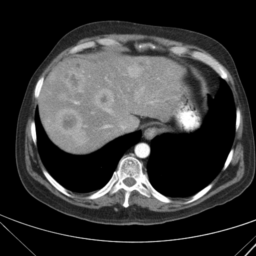

![]() |

| (a) | (b) | (c) | (d) |

Unsupervised Categorization: Our category discovery clusters are generally visually coherent within the cluster and size-balanced across clusters. However, image clusters formed only based on text information (of radiology reports) are highly unbalanced [49], with three clusters inhabiting the majority of images. Note that our method imposes no explicit constraint on the number of instances per cluster. Fig. 6 shows sample images and their top-10 associated key words from two randomly selected clusters (more results are provided in the supplementary material). The LDPO clusters are found to be clinically or semantically related to the corresponding key words, which describe presented anatomies, pathologies (e.g., adenopathy, mass), their associated attributes (e.g., bulky, frontal) and imaging protocols or properties.

The category discovery clusters employing our LDPO method are found to be more visually coherent and cluster-wise balanced in comparison to the results in [49] where clusters are formed only from text information ( radiology reports). Fig. 7 Left shows the image numbers for each cluster from the AlexNet-FC7-Topic setting. The numbers are uniformly distributed with a mean of 778 and standard deviation of 52. Fig. 7 Right illustrates the relation of clustering results derived from image cues or text reports [49]. Note that there is no instance-balance-per-cluster constraints in the LDPO clustering. The clusters in [49] are highly uneven: 3 clusters inhabit the majority of images. Fig. 6 shows sample images and top-10 associated key words from 5 randomly selected clusters (more results in the supplementary material). The LDPO clusters are found to be semantically or clinically related to the corresponding key words, containing the information of (likely appeared) anatomies, pathologies (e.g., adenopathy, mass), their attributes (e.g., bulky, frontal) and imaging protocols or properties.